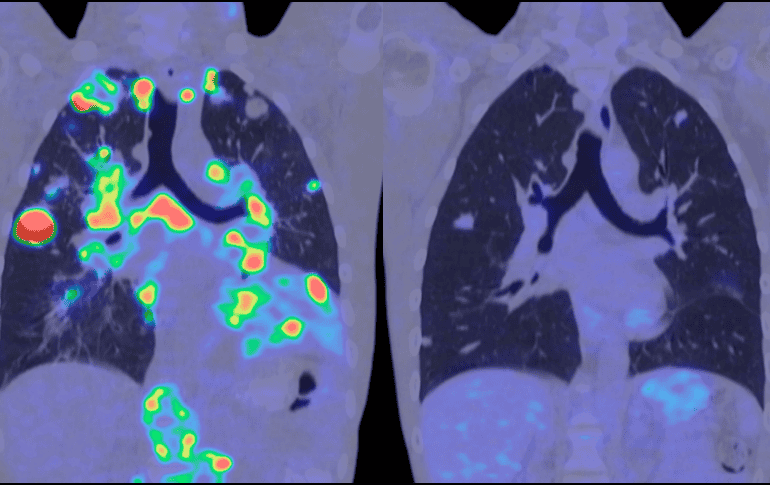

Entre los participantes había pacientes con cáncer de hígado, pulmón, ovario y estómago; con enfermedades hepáticas como la hepatitis B, la hepatitis C, con patología hepática relacionada con el alcohol y trastornos metabólicos; personas con nódulos pulmonares benignos; y participantes sanos.

Los autores señalan que MethylScan "puede funcionar como un radar de salud para el cuerpo". Al leer las señales de ADN en la sangre, puede determinar cuándo órganos específicos, como el hígado o los pulmones, están sometidos a estrés o dañados, incluso sin conocer la enfermedad de antemano.